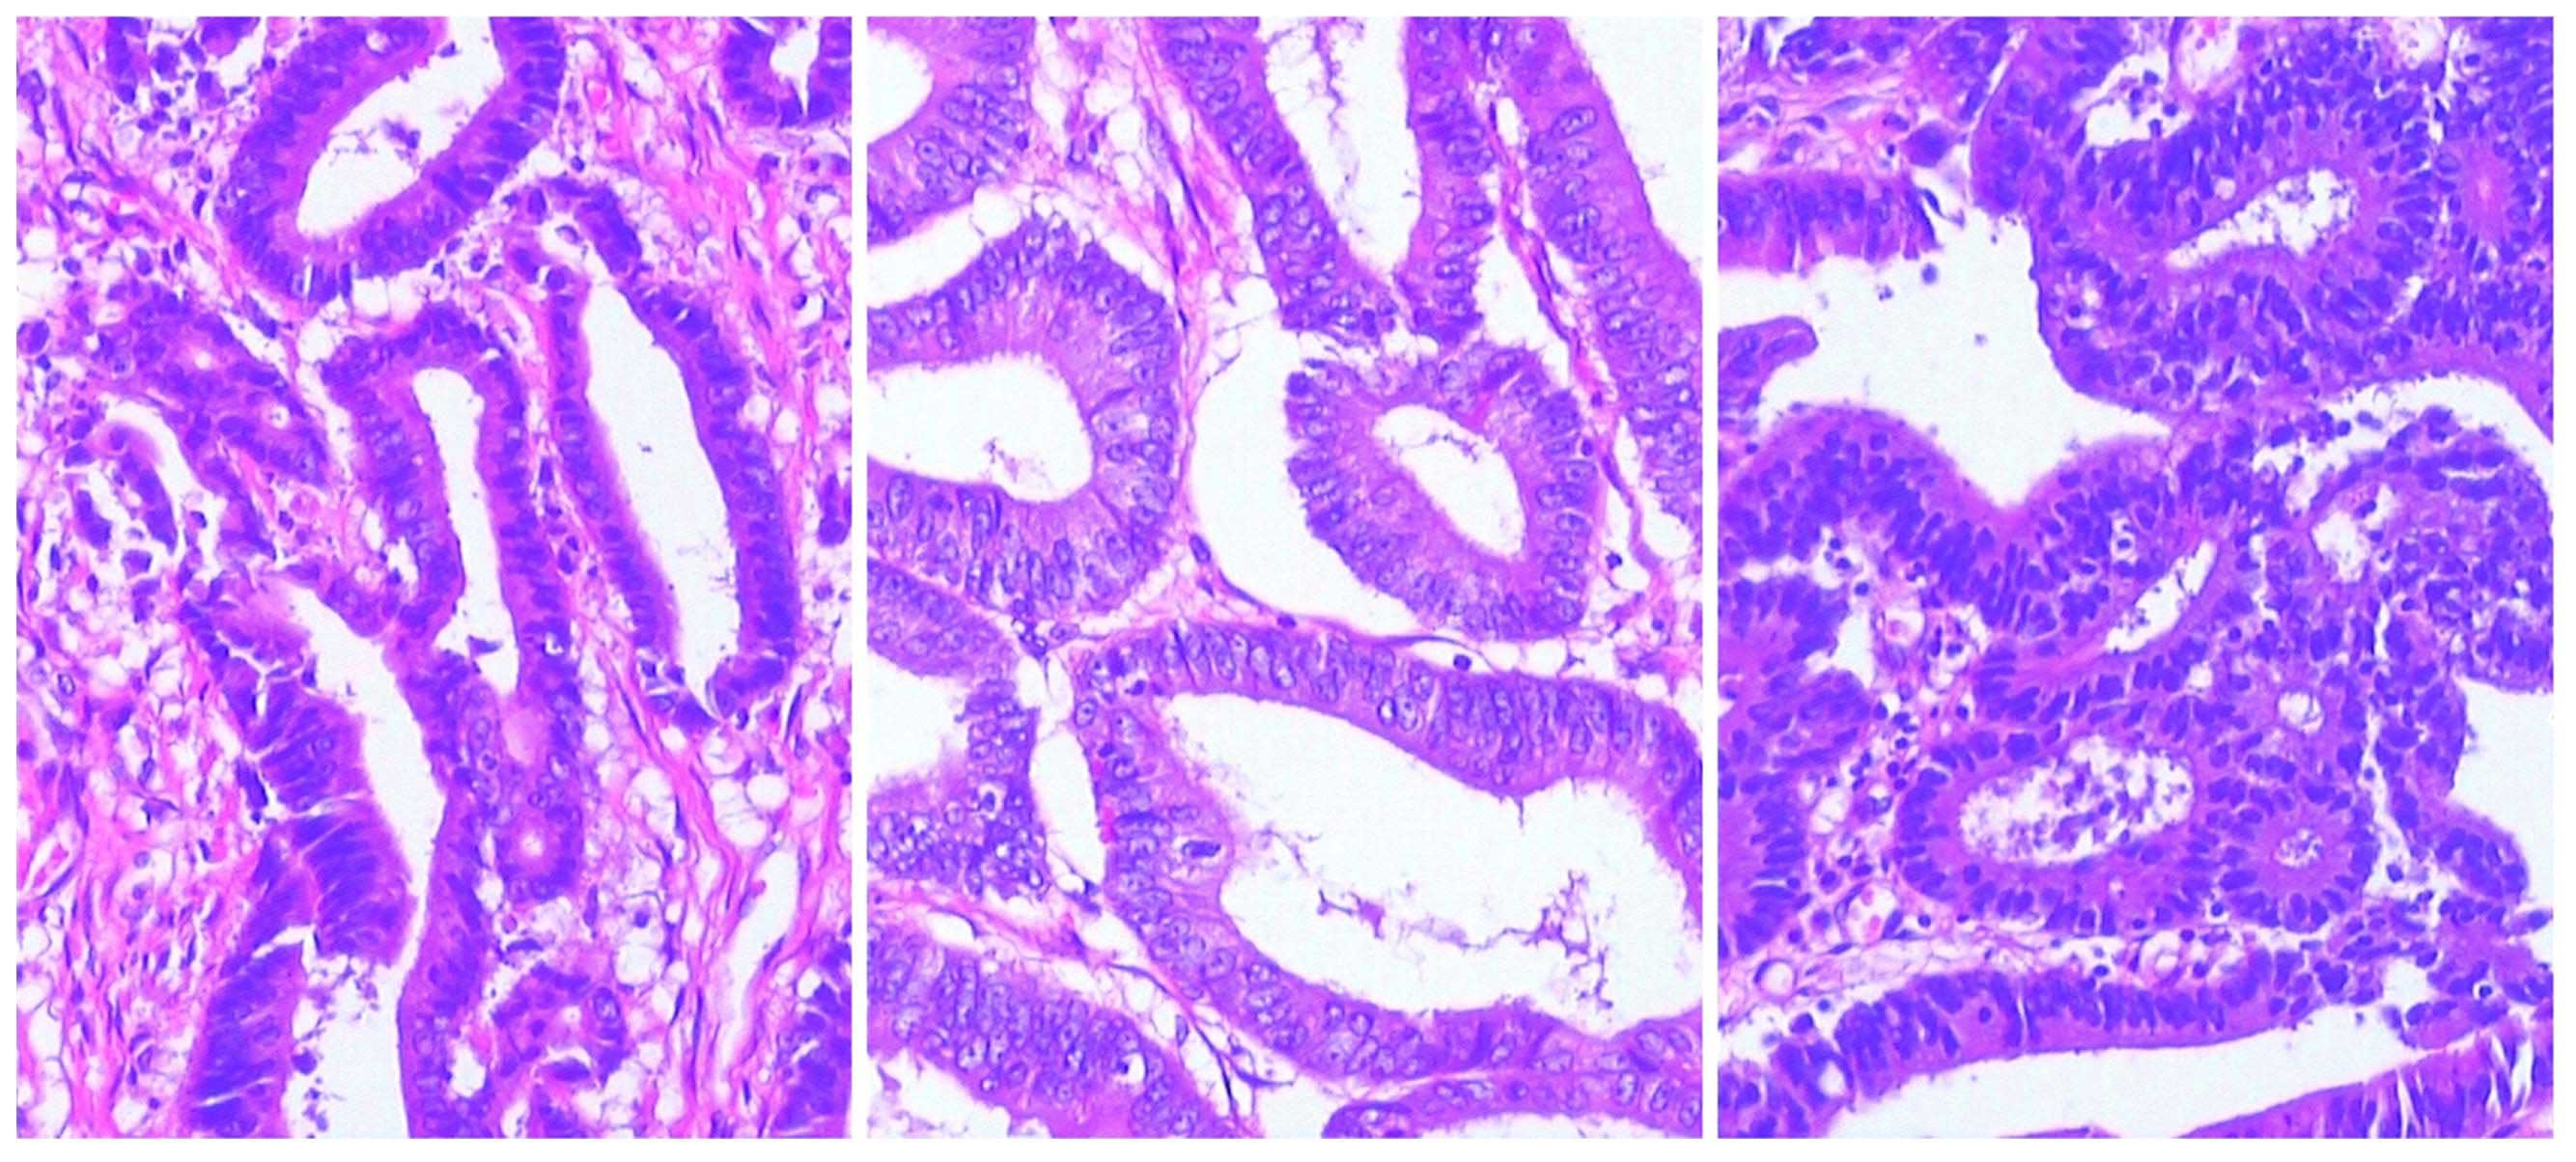

Laparoscopic subtotal colectomy for synchronous triple colorectal cancer: A case report

Synchronous colorectal cancers refer to the simultaneous occurrence of multiple colorectal tumors in a single patient, excluding any metastases from other organs. At present, radical surgery is considered the standard curative treatment; however, individualized surgical strategies depend on tumor location, the depth of invasion and the general health of the patient. In the present study, the case of a 52‑year‑old man who presented with a 2‑month history of abdominal pain that was accompanied by intermittent hematochezia and weight loss is reported. The patient had no family history of cancer. Computed tomography (CT) of the abdomen revealed intestinal wall thickness in the transverse colon and volvulus in the hepatic flexure of colon. Colonoscopy identified 3 tumors: The first tumor was located in the descending colon with lumen stenosis ~60 cm from the anal verge, the second tumor was located in the hepatic flexure of the colon, and the third tumor was located in the sigmoid colon, 23 cm from the anal verge. Subsequently, laparoscopic subtotal colectomy was performed and all three tumors were removed, and the diagnosis was confirmed by histopathological examination. The patient did not undergo chemotherapy following surgery, due to personal reasons. Subsequent to 19 months of follow‑up examinations using CT and colonoscopy every 6 months, the patient exhibited no signs of recurrence. Thus, laparoscopic subtotal colectomy represents an effective surgical approach for the treatment of synchronous colorectal cancer following imaging and endoscopic diagnosis.

Figure 1

Figure 2

Figure 3

Figure 4